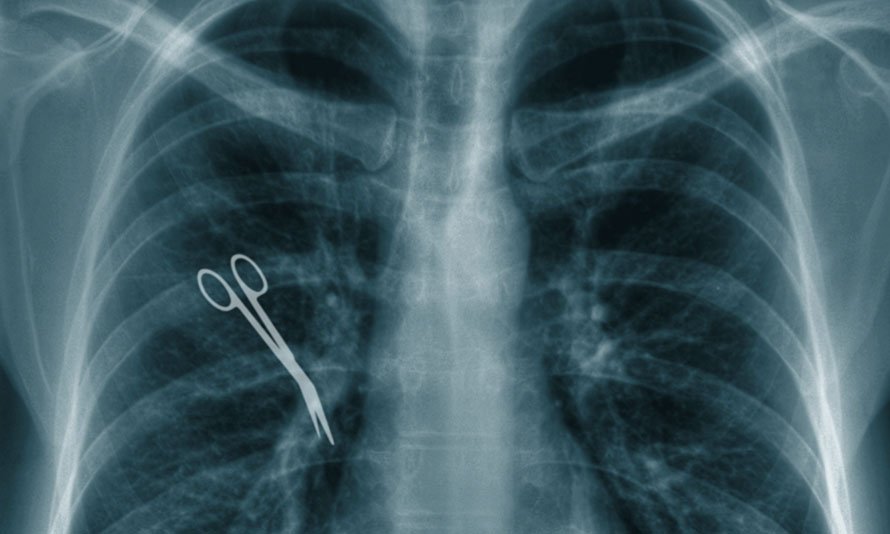

Surgical Clamp Left Inside Patient

Year: 2018

Location: Manhattan, NY

Details: During a complex cardiovascular surgery at a Manhattan hospital, a surgical clamp was left inside a patient named Henry Thompson. Post-surgery, Henry experienced severe chest pain and difficulty breathing. A series of diagnostic tests revealed the presence of the clamp, necessitating another invasive surgery to remove it. The hospital faced a malpractice lawsuit, and Henry was awarded a significant settlement for his pain, medical expenses, and the impact on his quality of life.